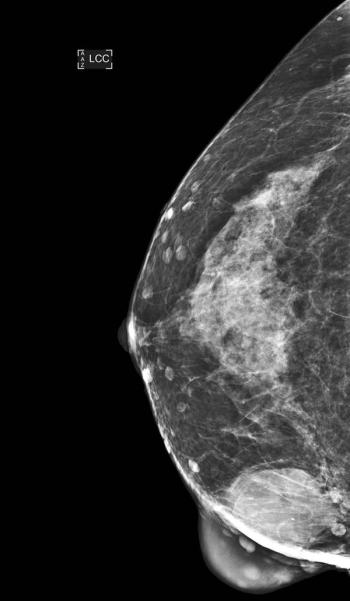

Case History: 67-year-old female with progressive increase in size of left breast for five years.